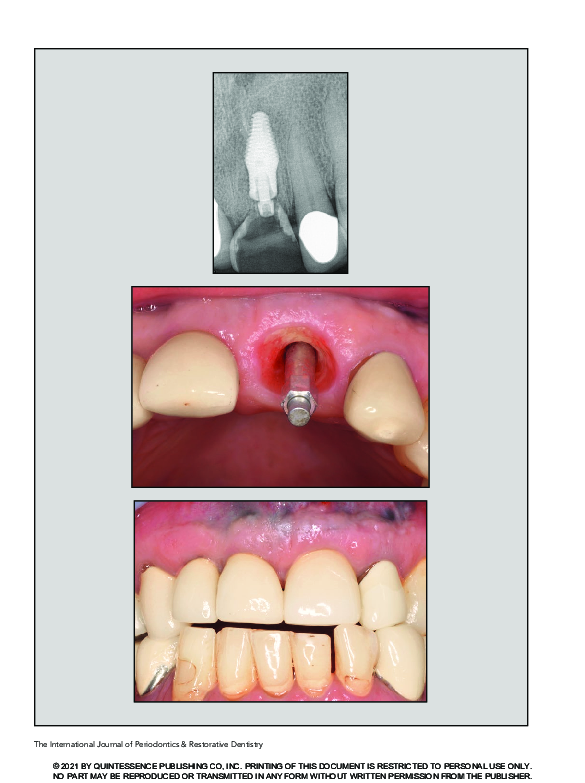

(PDF) A Novel Implant Design for Immediate Extraction Sites Novel Implant novel implant and abutment surface designs were produced and characterized using surface chemical. this prospective study evaluated the survival rate of immediately loaded anatomically tapered implants with a dual. the novel implant (hybrid implant) showed good stability and. the nobelreplace conical connection implant can be considered as a valuable treatment option for immediate implant. this. Novel Implant.